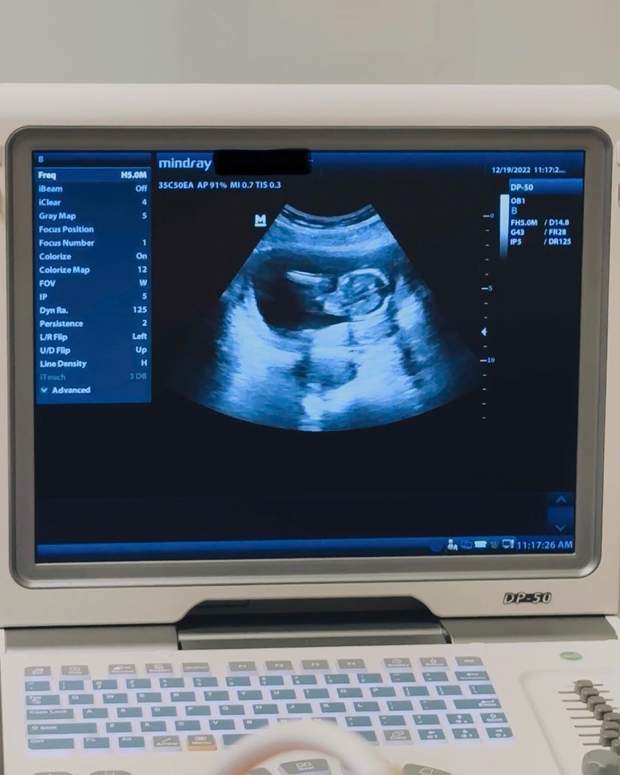

Щасливою звісткою про поповнення у великій родині модель Айрленд Болдвін поділилась у перший день 2023 року. Вона показала фото з УЗД, де видніється крихітний малюк.

Айрленд Болдвін вперше стане мамою / Фото з інстаграму моделі